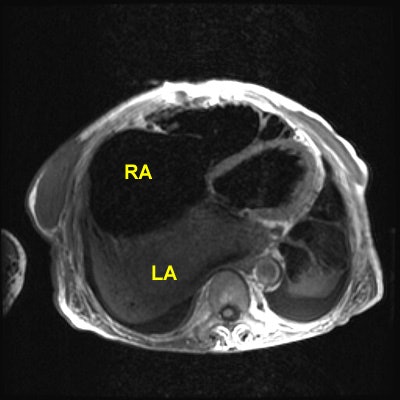

Rheumatic Fever

The patient shown below had a long history of valvular heart disease secondary to rheumatic fever. Both mitral and tricuspid valves were involved. There is massive right atrial (RA) dilatation. The left atrium is also massively dilated. Increased signal within the left atrium is related to slow flow.